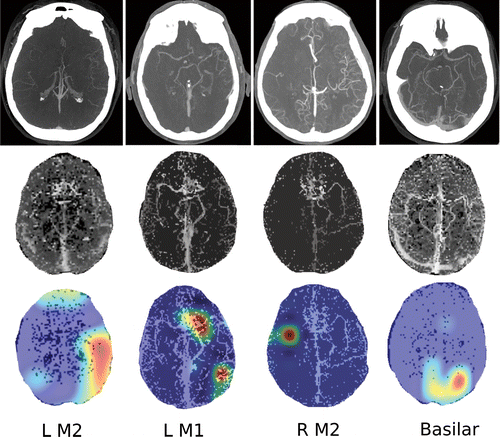

Images show four separate patients with large vessel occlusions correctly predicted by the algorithm. The top row shows a representative CT slice from the delayed venous phase CT angiography. The middle row shows the preprocessed maximum intensity projection images that function as the input to the model. The bottom row are overlaid heat maps, with areas in red showing the most discriminative regions. Notice these so-called hot regions correlate with the occlusion location (respectively: left [L] M2, L M1, right [R] M2, basilar) in each patient. Courtesy: Radiology